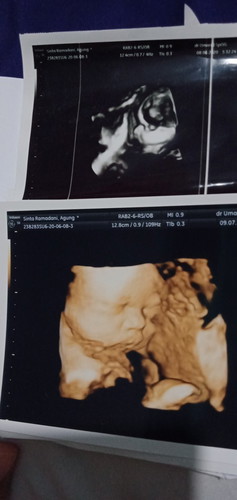

usg pertama msuk 7 bulan dokter bilang bayinya sungsang,,,alhamdullilahhh karena rajin sujud pas usg masuk 8 bulan kepala bayinya udah di bawahhh,,,hpl tgl 1 september semoga bayinya tetap dalam posisi normal sampai kelahirann dan dipermudah kelahirannya mohonn doanya ya bunda bunda๐ค๐ค,,, sebenarnay ini anak peratamaku jadi masih banyak yang belumm aku ketahui dan aku pelajari jadi menjelang kelahiran bunda bunda berkenan untuk kasih saran apa aja yang bisa aku terapkan nantinya agar aku bisa lahirann normalll mohonn bantuannnya ya bunda bundaaa๐๐๐๐โบ๏ธ